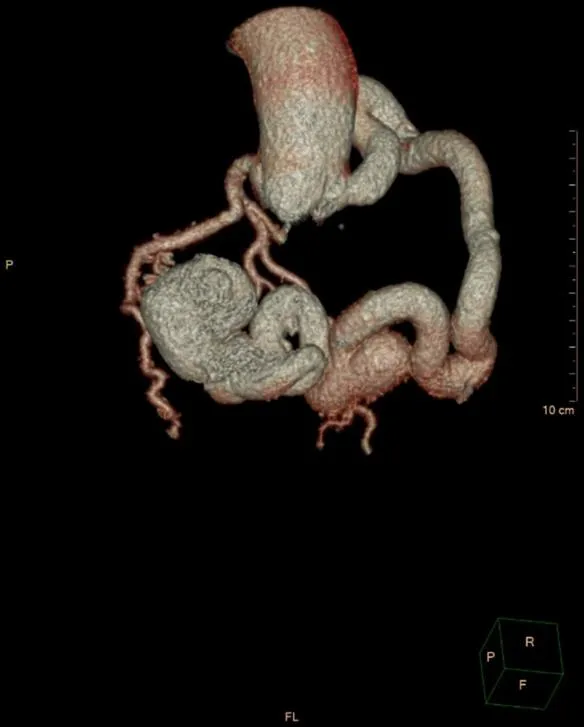

病史摘要:64岁男性患者,因“反复胸闷2月”入院。既往有10年高血压病史,最高血压160/100 mmHg,长期服药后血压控制在130/80 mmHg左右;20年前行胆囊切除术,有胰腺炎病史,否认糖尿病等慢性及传染病史。劳累后心前区闷痛,持续约5分钟,休息可缓解,入院时仍时有胸闷。 诊疗过程:查体血压130/80 mmHg,心率80次/分,律不齐,主动脉瓣第一听诊区闻及收缩期喷射样杂音